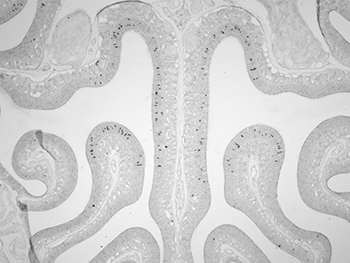

To do this, he replaces a gene in certain nerve cells of mice. These olfactory (Oal-FAK-tuh-ree) cells respond to scents by emitting light — fluorescing. By looking for that telltale light, he can spot which nerve cell is related to which odor receptor — and therefore, to which smell. So far, McClintock has “mapped” receptors for 10 different smells.